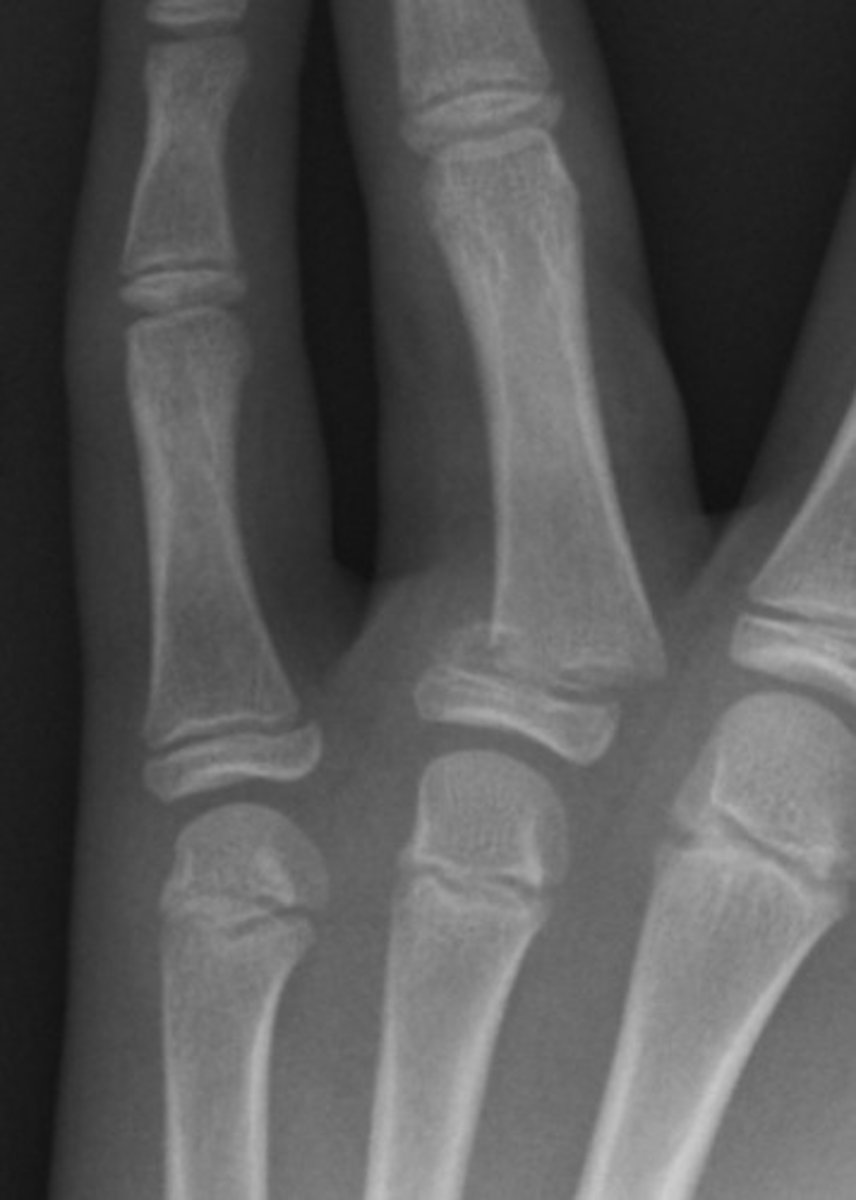

There is a transverse to slightly oblique fracture through the waist of the scaphoid, with no significant displacement or carpal malalignment. Additionally, there is an oblique intra-articular fracture at the base of the first metacarpal, extending into the carpometacarpal joint. The distal metacarpal fragment is displaced proximally and dorsally, consistent with a Bennett's fracture, with associated subluxation at the CMC joint.

SH type 3

SH 1

SH 4